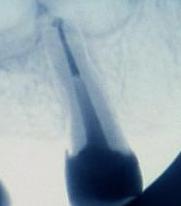

Evidentemente el punto más importante, que determina el tipo de restauración a realizar es la cantidad y distribución de tejido dental sano que se conserva después del tratamiento. En el 90 por ciento de los casos, lo que motiva tener que realizar un tratamiento endodóntico, es la presencia de una caries de ciertas dimensiones en alguna parte de la corona denta y que ha afectado al tejido pulparl. Por otra parte la cavidad del acceso a los conductos radiculares para realizar la endodoncia debe siempre hacerse de una manera concreta, garantizando la vía más recta a dichos conductos.Todo esto hace que la cantidad de tejido dental remanente pueda disminuir considerablemente.

Dependiendo de la situación, el tipo de restauración más adecuada puede ir desde la simple obturación de la cavidad de acceso a la endodoncia, hasta el uso de pernos radiculares o diferentes tipos de recubrimientos para la corona del diente.

Por estos motivos en ocasiones es necesario recubrir el diente completamente para protegerlo al máximo. También, si la cantidad de tejido dentario es muy limitada, puede ser necesario el uso de refuerzos radiculares denominados pernos o postes.